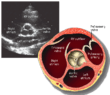

|  |  |  |  |  short axis | ||||||

| Each figure contains a TTE with a black background, and a corresponding colored illustration. | Patrick J. Lynch and C. Carl Jaffe, Yale University, 2006. | ||||||||||

| Click on a figure to enlarge it and see some parts of the heart identified. RV, right ventricle; LV, left ventricle; RA, right atrium; LA, left atrium; TV, tricuspid valve; MV, mitral valve; AV, aortic valve; RVOT, right ventricular outflow tract; LVOT, left ventricular outflow tract | |||||||||||